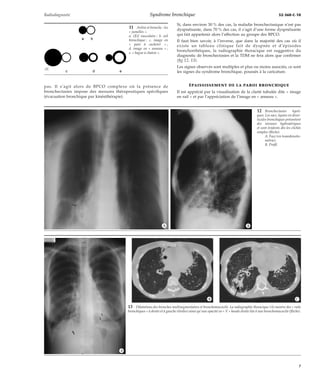

14 Dilatation des bron-ches

multisegmentaires.

A. La radiographie

thoracique montre des

« rails » bronchiques

en lobaire moyen (flè-ches).

B. La tomodensitomé-trie

précise les nom-breux

territoires at-teints

de bronchec-tasies

cylindriques et

moniliformes débu-tantes

(flèches : S5D

et S7D).

*A

*B

15 Bronchectasies lobai-res

moyennes et bronchio-lectasies

périphériques.

thoracique constate

un bord cardiaque

droit effacé et des

ébauches de « rails

bronchiques » (tête de

flèche).

B, C. La tomodensito-métrie

enregistre des

dilatations des bron-ches

en S5D mais

aussi des bronchiolec-tasies

sous-pleurales

dans l’ensemble du

lobe moyen (têtes de

flèches).

*C